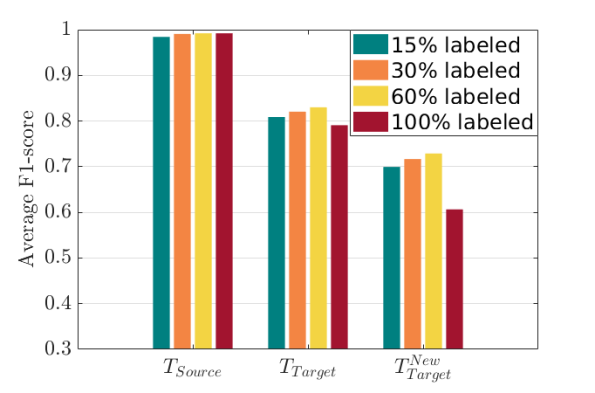

To explore the importance of labeled data, we evaluate the performance of MIDNet and MIDNet+ based on using and labeled data during training. Fig. 9 (a) shows the average F1-score on three groups of test data. From this figure, we observe that the classification performance improves with increasing labeled data.

From Fig. 9 (b), we observe that classification performance improves with the increase of labeled data in most cases. However, the performance reaches its peak after a certain percentage of labeled data is added. For example, the peak point is in this experiment.

The performance of semi-supervised learning usually positively correlates with the percentage of labeled data. In our experimental setting, excessive labeled data may lead to increased class imbalance. This may result in slightly decreased classification performance in Fig. 9 (b) when the percentage of labeled training data increases from (i.e., all classes contain the same number of labeled images: 951 images) to (i.e., Abdominal: 1448 labeled images vs. Lips: 1760 labeled images). A similar observation is made for a digits classification task in Appendix.

To explore the importance of labeled data, we evaluate the performance of MIDNet based on using and labeled data during training. Fig. 15 shows the average F1-score of these experiments on three groups of test data. From this figure, we observe that the classification performance only slightly improves with increasing labeled data. This indicates that MIDNet is capable of achieving expected performance with sparsely labeled data. Additionally, excessive labeled data may lead to increased class imbalance. This may result in decreased classification performance as shown in Fig. 15 when the percentage of labeled training data increased from (i.e., all classes contain the same number of labeled images: 4294 images) to (i.e., Digit 1: 10768 labeled images vs. Digit 5: 4336 labeled images).